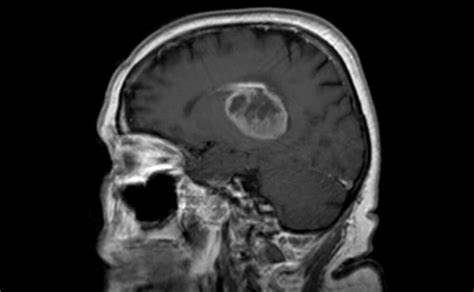

试图寻找该疾病治疗方法的研究人员表示,较致命的脑癌形式卷土重来,因为肿瘤通过招募附近健康组织的帮助来适应治疗。 一项由包括利兹大学专家在内的团队进行的新研究发现...

试图寻找该疾病治疗方法的研究人员表示,较致命的脑癌形式卷土重来,因为肿瘤通过招募附近健康组织的帮助来适应治疗。

一项由包括利兹大学专家在内的团队进行的新研究发现,在治疗的反应中,高级别神经

胶质瘤似乎会重塑周围的大脑环境,可能会与附近的神经元和免疫细胞产生相互作用,从而保护肿瘤细胞并隐藏它们免受身体防御的影响。

研究小组还发现,低级别肿瘤通常会产生一种新的突变,使细胞开始更快地分裂,有可能使它们变成更高级别的形式。

神经胶质瘤脑瘤是少见的,但诊断是毁灭性的,因为目前没有治愈。低级别胶质瘤的存活率高于高级别胶质瘤,但通常会发展为高级别胶质瘤。90%以上的高级别肿瘤患者在五年内死亡。

研究人员正在调查为什么神经胶质瘤会发展成更高级别的形式,以及为什么它们在治疗后存活并继续生长。

随着时间的推移,他们收集了神经胶质瘤从低级到高级的多个样本,以及治疗前后的样本。然后他们观察细胞是如何变化和适应的,看看他们是否能找到阻止它们的方法,使用新的药物。